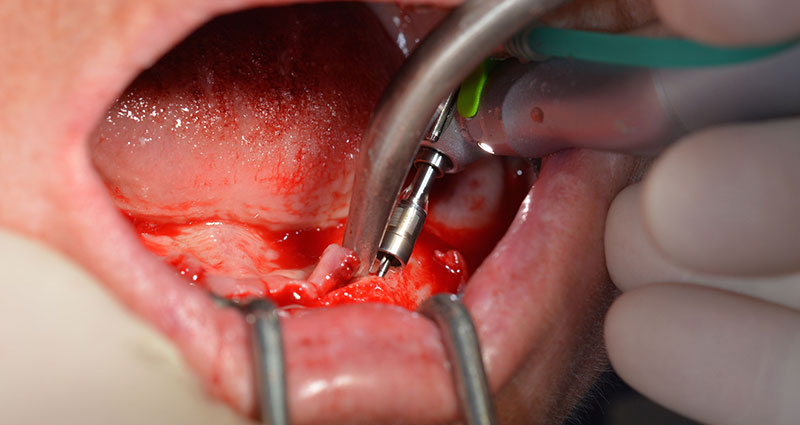

След отстраняване на частичното обеззъбяване в долната челюст, алвеоларният гребен е разкрит от 37 до 47.

Изходът на долночелюстния нерв е първоначално идентифициран като ограничена анатомична структура и, след това, кортикалната кост на гребена е загладена с прав наконечник и голям борер с розовиден профил  (Фиг. 4).